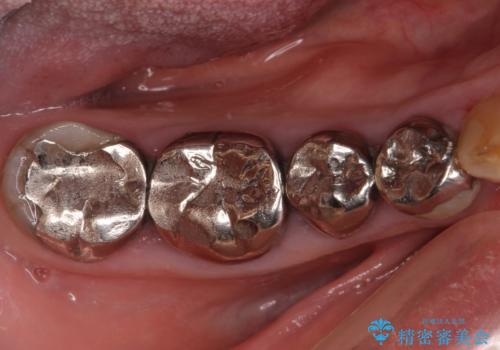

全ての奥歯の銀歯をセラミックに メタルフリー治療

- 奥歯に装着されている銀歯を全て外したいとのことで来院された患者様です。

土台に含まれている金属も含め、奥歯の金属は全て除去し、オールセラミッククラウンやセラミックインレーにて治療することとしました。